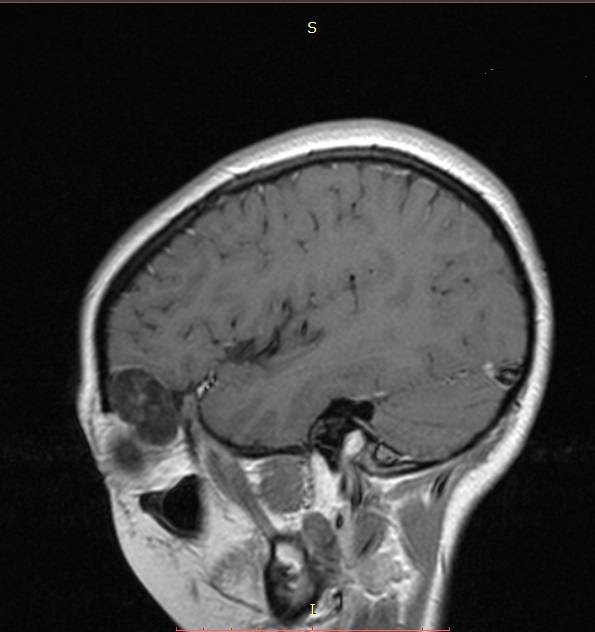

One of the cases involving the use of this technique was a teenager who underwent surgery at the end of 2020. The patient presented with proptosis (bulging eyes) and pain in the left superciliary area.

Examination and imaging revealed a left orbital mass spreading to the orbit walls and cranial cavity.

| MRI before surgery | 3D modeling before surgery The mass is marked in pink |